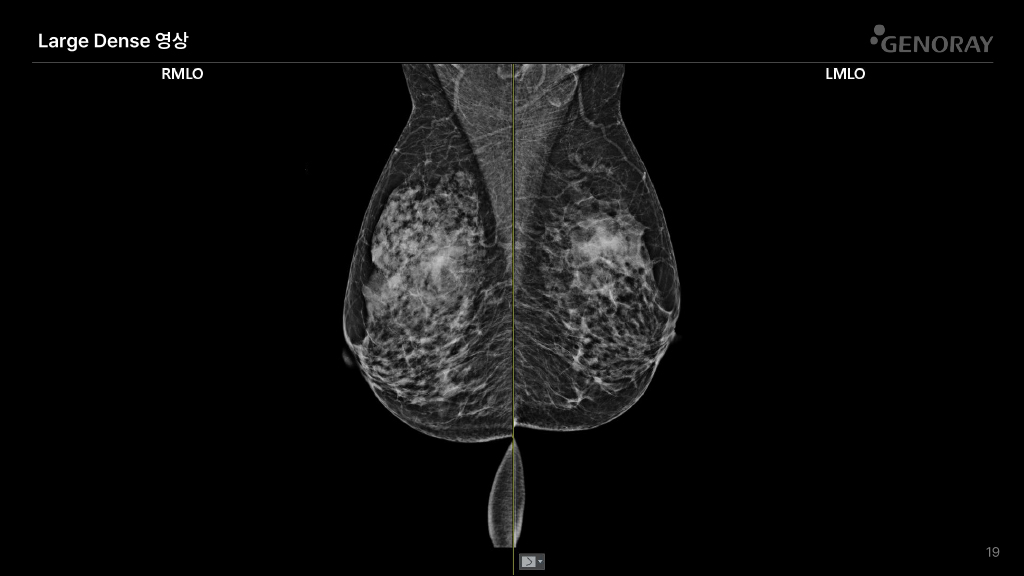

CLINICAL IMAGES

오랜 경험을 통해 축적된 노하우로 진단영상을 제공합니다.